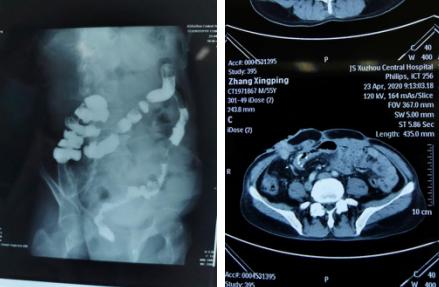

术前灌肠造影片(左图)

术前CT小肠造口状态(右图)